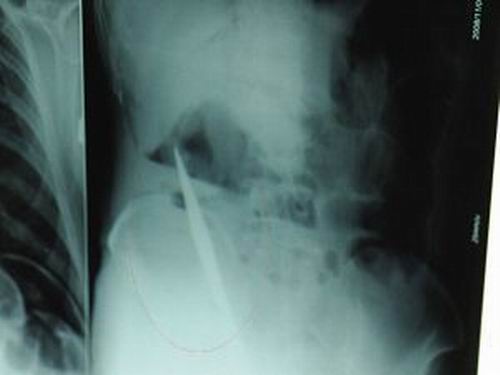

X光片上,尖刀清晰可見。

從男子體內(nèi)取出的尖刀足足有19厘米長。

江蘇銅山一58歲男子因服毒被送到醫(yī)院搶救,可醫(yī)生采取搶救措施后卻發(fā)現(xiàn)效果不佳。后來經(jīng)細(xì)致檢查,醫(yī)生有了個(gè)驚人的發(fā)現(xiàn),該男子的體內(nèi)竟然有一把尖刀,醫(yī)生通過手術(shù)將位于其腹部右側(cè)橫結(jié)腸下緣的尖刀取了出來。這把尖刀足足有19厘米長!據(jù)醫(yī)生推測,這把刀應(yīng)該是從肛門推進(jìn)體內(nèi)的,不知男子為何想以如此殘酷的方式結(jié)束自己生命。由于搶救及時(shí),該男子已暫時(shí)脫離危險(xiǎn)。

昨天(11月6日)上午,記者在徐州礦務(wù)集團(tuán)總醫(yī)院重癥監(jiān)護(hù)室見到了這名男子,目前他雖然已經(jīng)恢復(fù)了意識,但還不能開口說話,需要呼吸機(jī)輔助呼吸。據(jù)醫(yī)生介紹,4日中午12時(shí)左右,這名男子因服毒輕生被緊急送到醫(yī)院進(jìn)行搶救,之前,這名男子已經(jīng)在當(dāng)?shù)剜l(xiāng)鎮(zhèn)醫(yī)院進(jìn)行了近20小時(shí)的治療,但效果不佳。“病人被轉(zhuǎn)院到礦總院時(shí)已神志不清,血壓極低,處于休克狀態(tài)。”救護(hù)人員給男子洗胃、初步處理以后,發(fā)現(xiàn)男子呼吸急促,于是趕緊給他拍片檢查。結(jié)果讓所有的醫(yī)生大吃一驚,竟有一把尖狀異物橫在該男子腹腔內(nèi)!當(dāng)天下午5時(shí)30分,輕生男子被推上了手術(shù)臺。經(jīng)過40多分鐘的手術(shù),該男子腹腔被打開,手術(shù)醫(yī)生發(fā)現(xiàn),男子體內(nèi)的金屬狀異物竟然是一把長19厘米的尖刀!